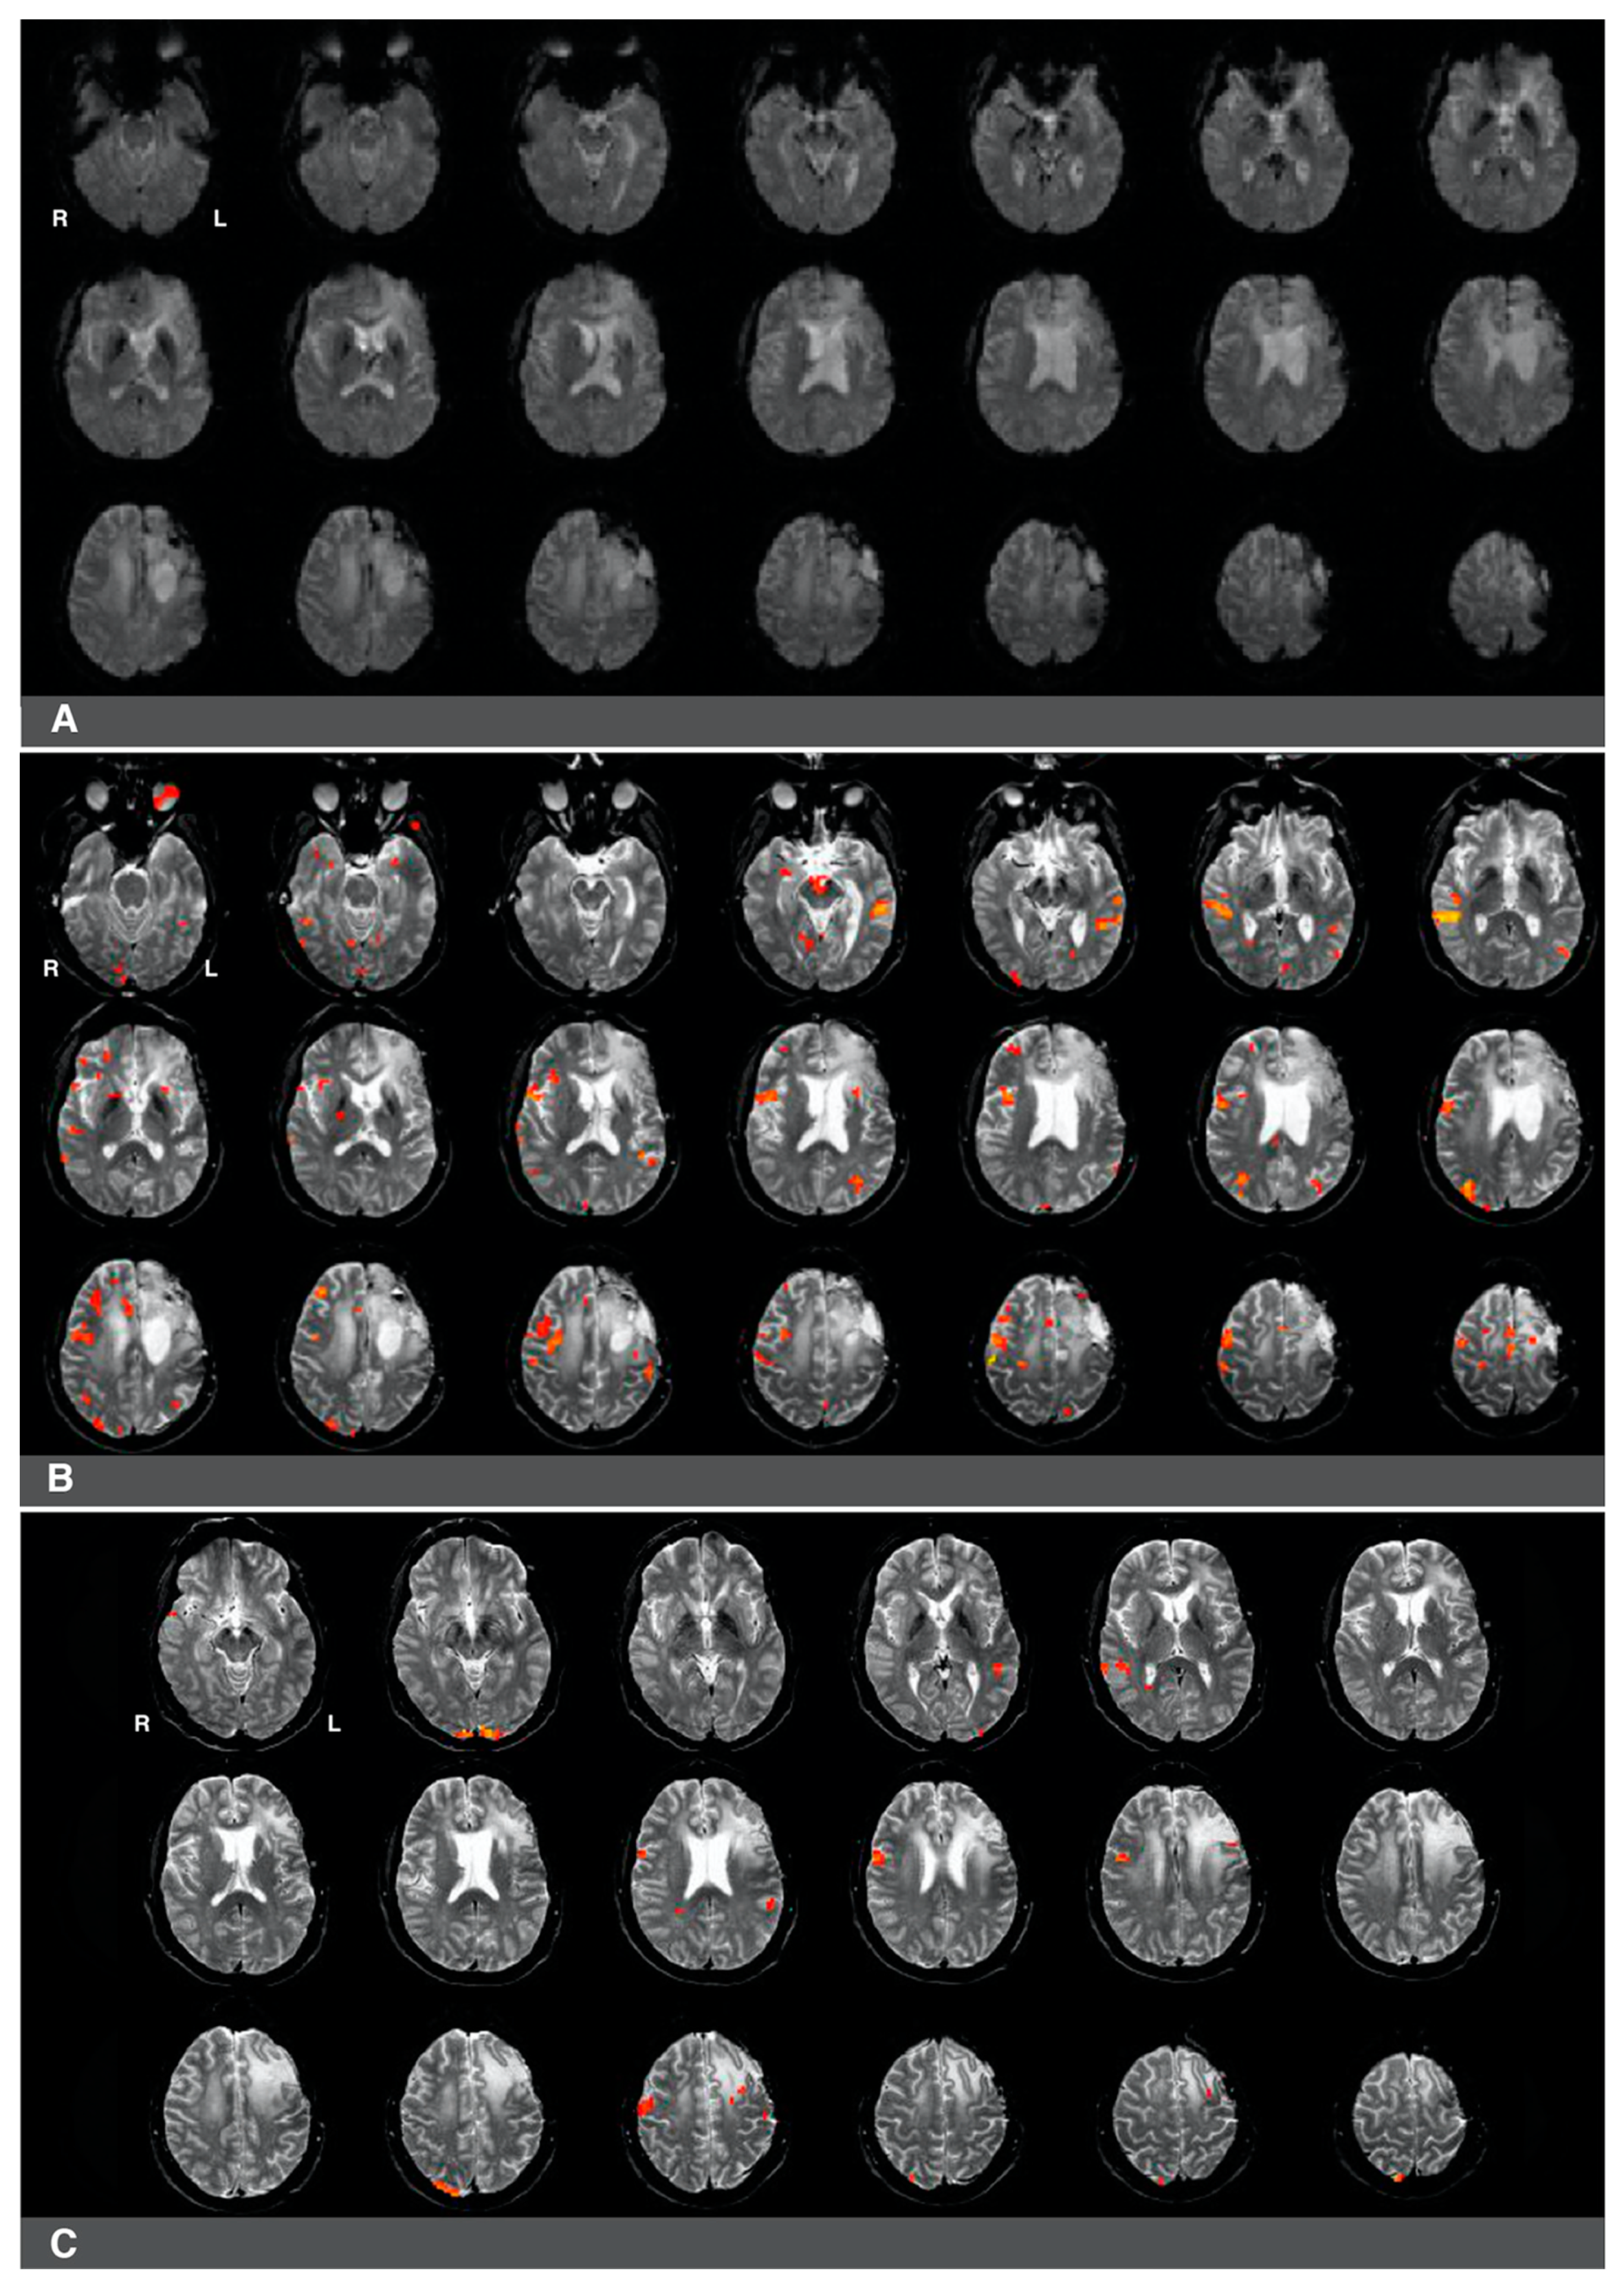

While language laterality values were significantly lower in patients who underwent prior surgery (whole-hemisphere LI and Broca’s area LI), we noted a high degree of individual heterogeneity in this group in terms of the range of language laterality values observed. This considerable variability suggests that these patients may be differentially affected by several factors associated with the previous resection (e.g., the presence of surgical hardware), glioma regrowth (e.g., glioma size, glioma grade, edema), and the amount of subsequent right hemisphere engagement in language. Signal artifacts constitute a particular challenge in interpreting the results of preoperative fMRI since activations in eloquent language sites can be obscured. In cases where surgical hardware and/or edema may impair fMRI activations, it is more challenging to evaluate whether right hemisphere activity during language tasks (if present) is compensatory in nature or whether it is caused by pseudo-reorganization (i.e., disinhibition of the right hemisphere) [8,11,16,33,34]. Figure 4 and Figure 5 present two cases that illustrate several challenges associated with interpreting the results of presurgical language fMRI in individuals who underwent a previous resection.

Figure 4.

Right-hemisphere activations in a (clinically confirmed) left language-dominant patient with a high-grade glioma in the left hemisphere. Panel (A): a raw functional image with a notable absence of activation in the left frontal region corresponding to Broca’s area. The absence of activation may be related to artifact and edema from prior resection in the area. Panel (B): Language activations consistent with Broca’s area observed in the right hemisphere during pre-surgical fMRI. Panel (C): Prior fMRI from six months earlier indicates Broca’s representation in the left hemisphere.

The first case was a 47-year-old, left-handed male with a diagnosis of a left frontal glioma. The patient was diagnosed with stage III oligoastrocytoma, and he suffered from significant aphasia. The patient underwent chemo- and radiotherapy and had a history of seizures. His fMRI language laterality based on the whole-hemisphere approach was −0.5. Language laterality was −1 using Broca’s ROI and 0.05 using Wernicke’s ROI. As shown in Figure 4, the eloquent cortex was identified in both the right and left hemispheres in this patient. There was a notable absence of activation in the left frontal region corresponding to Broca’s area that may be related to artifact and edema from prior resection in the area (Figure 4A). Language activations consistent with Broca’s area were observed in the right hemisphere in images four and seven of the second row and the first image of the third row (Figure 4B). Prior fMRI from six months earlier indicates Broca’s representation in the left hemisphere (Figure 4C, row two, slice five). The eloquent language cortex in this area was confirmed with speech arrest during awake mapping. Additionally, the patient experienced significant language decline in the last two months proceeding the latest clinical fMRI. Thus, while the activity in the right hemisphere seemed to have some compensatory effect on language function, the patient was not right hemisphere dominant for language, as the whole-hemisphere-based and Broca’s-based language laterality might suggest. Laterality index values obtained from Wernicke’s region appeared more reliable in this case.